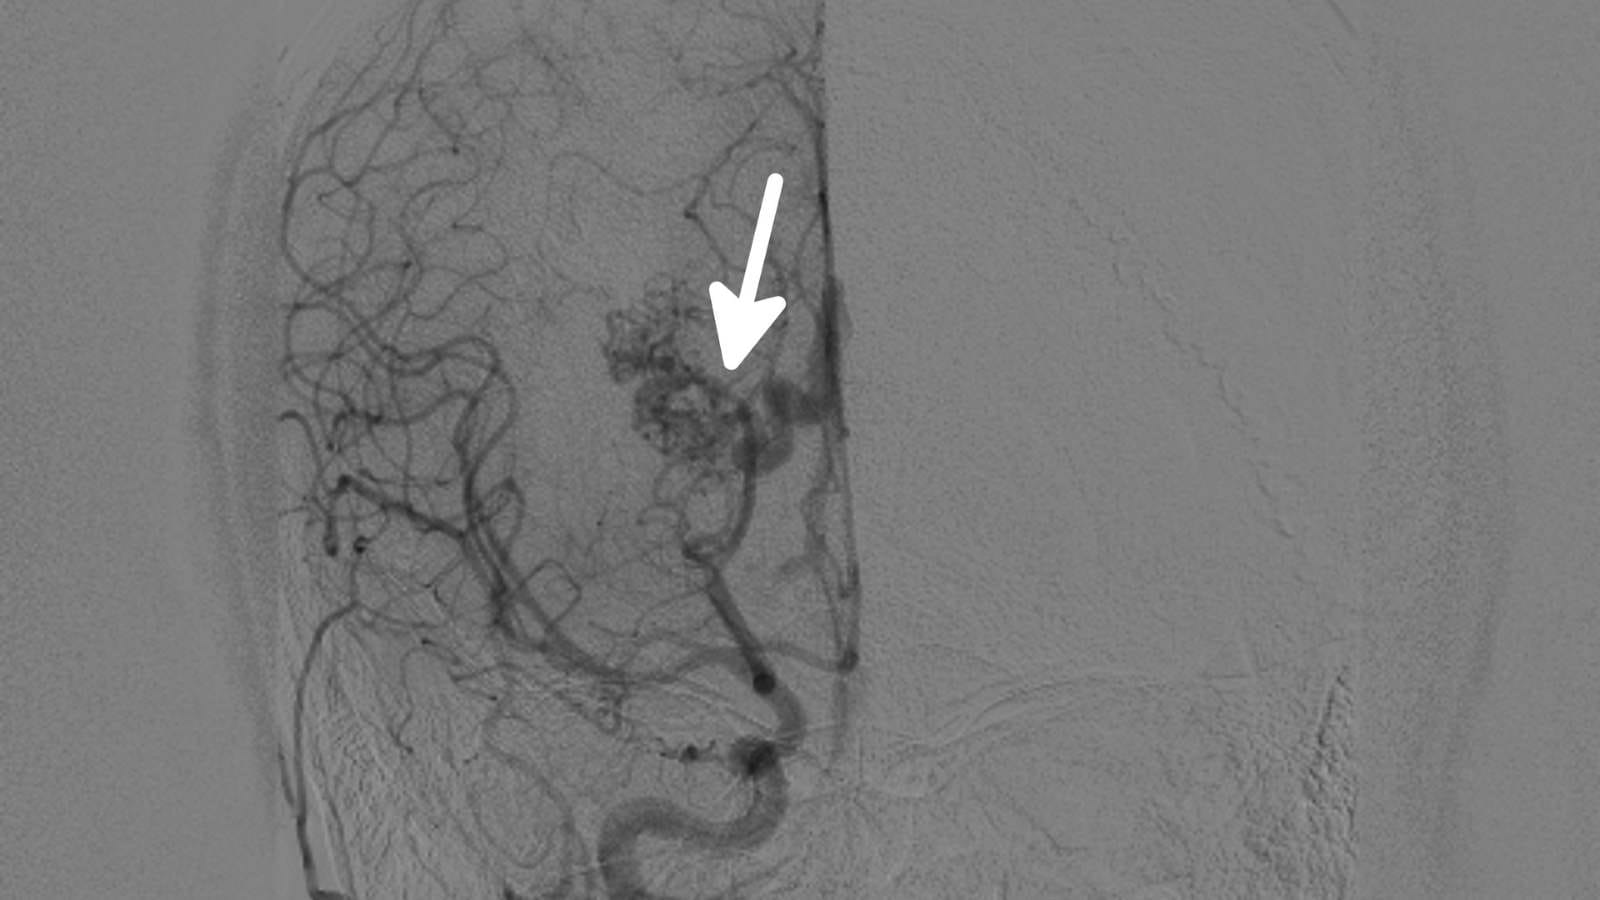

Y stent eşlikli kapalı anevrizma tedavisi